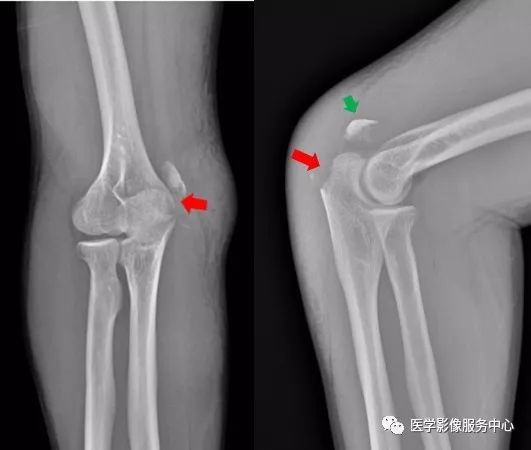

膝关节

图片

右侧胫骨粗隆可见低密度骨折线,骨折处稍分离移位,考虑为右侧胫骨粗隆骨折。